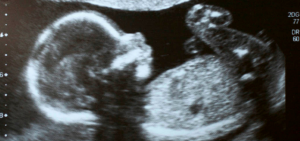

En las redes sociales se ha viralizado un video donde muestra una ecografía donde un bebé parece sonreir y saludar.

Te dejamos el video para que lo veas por ti mismo a partir del segundo 5: